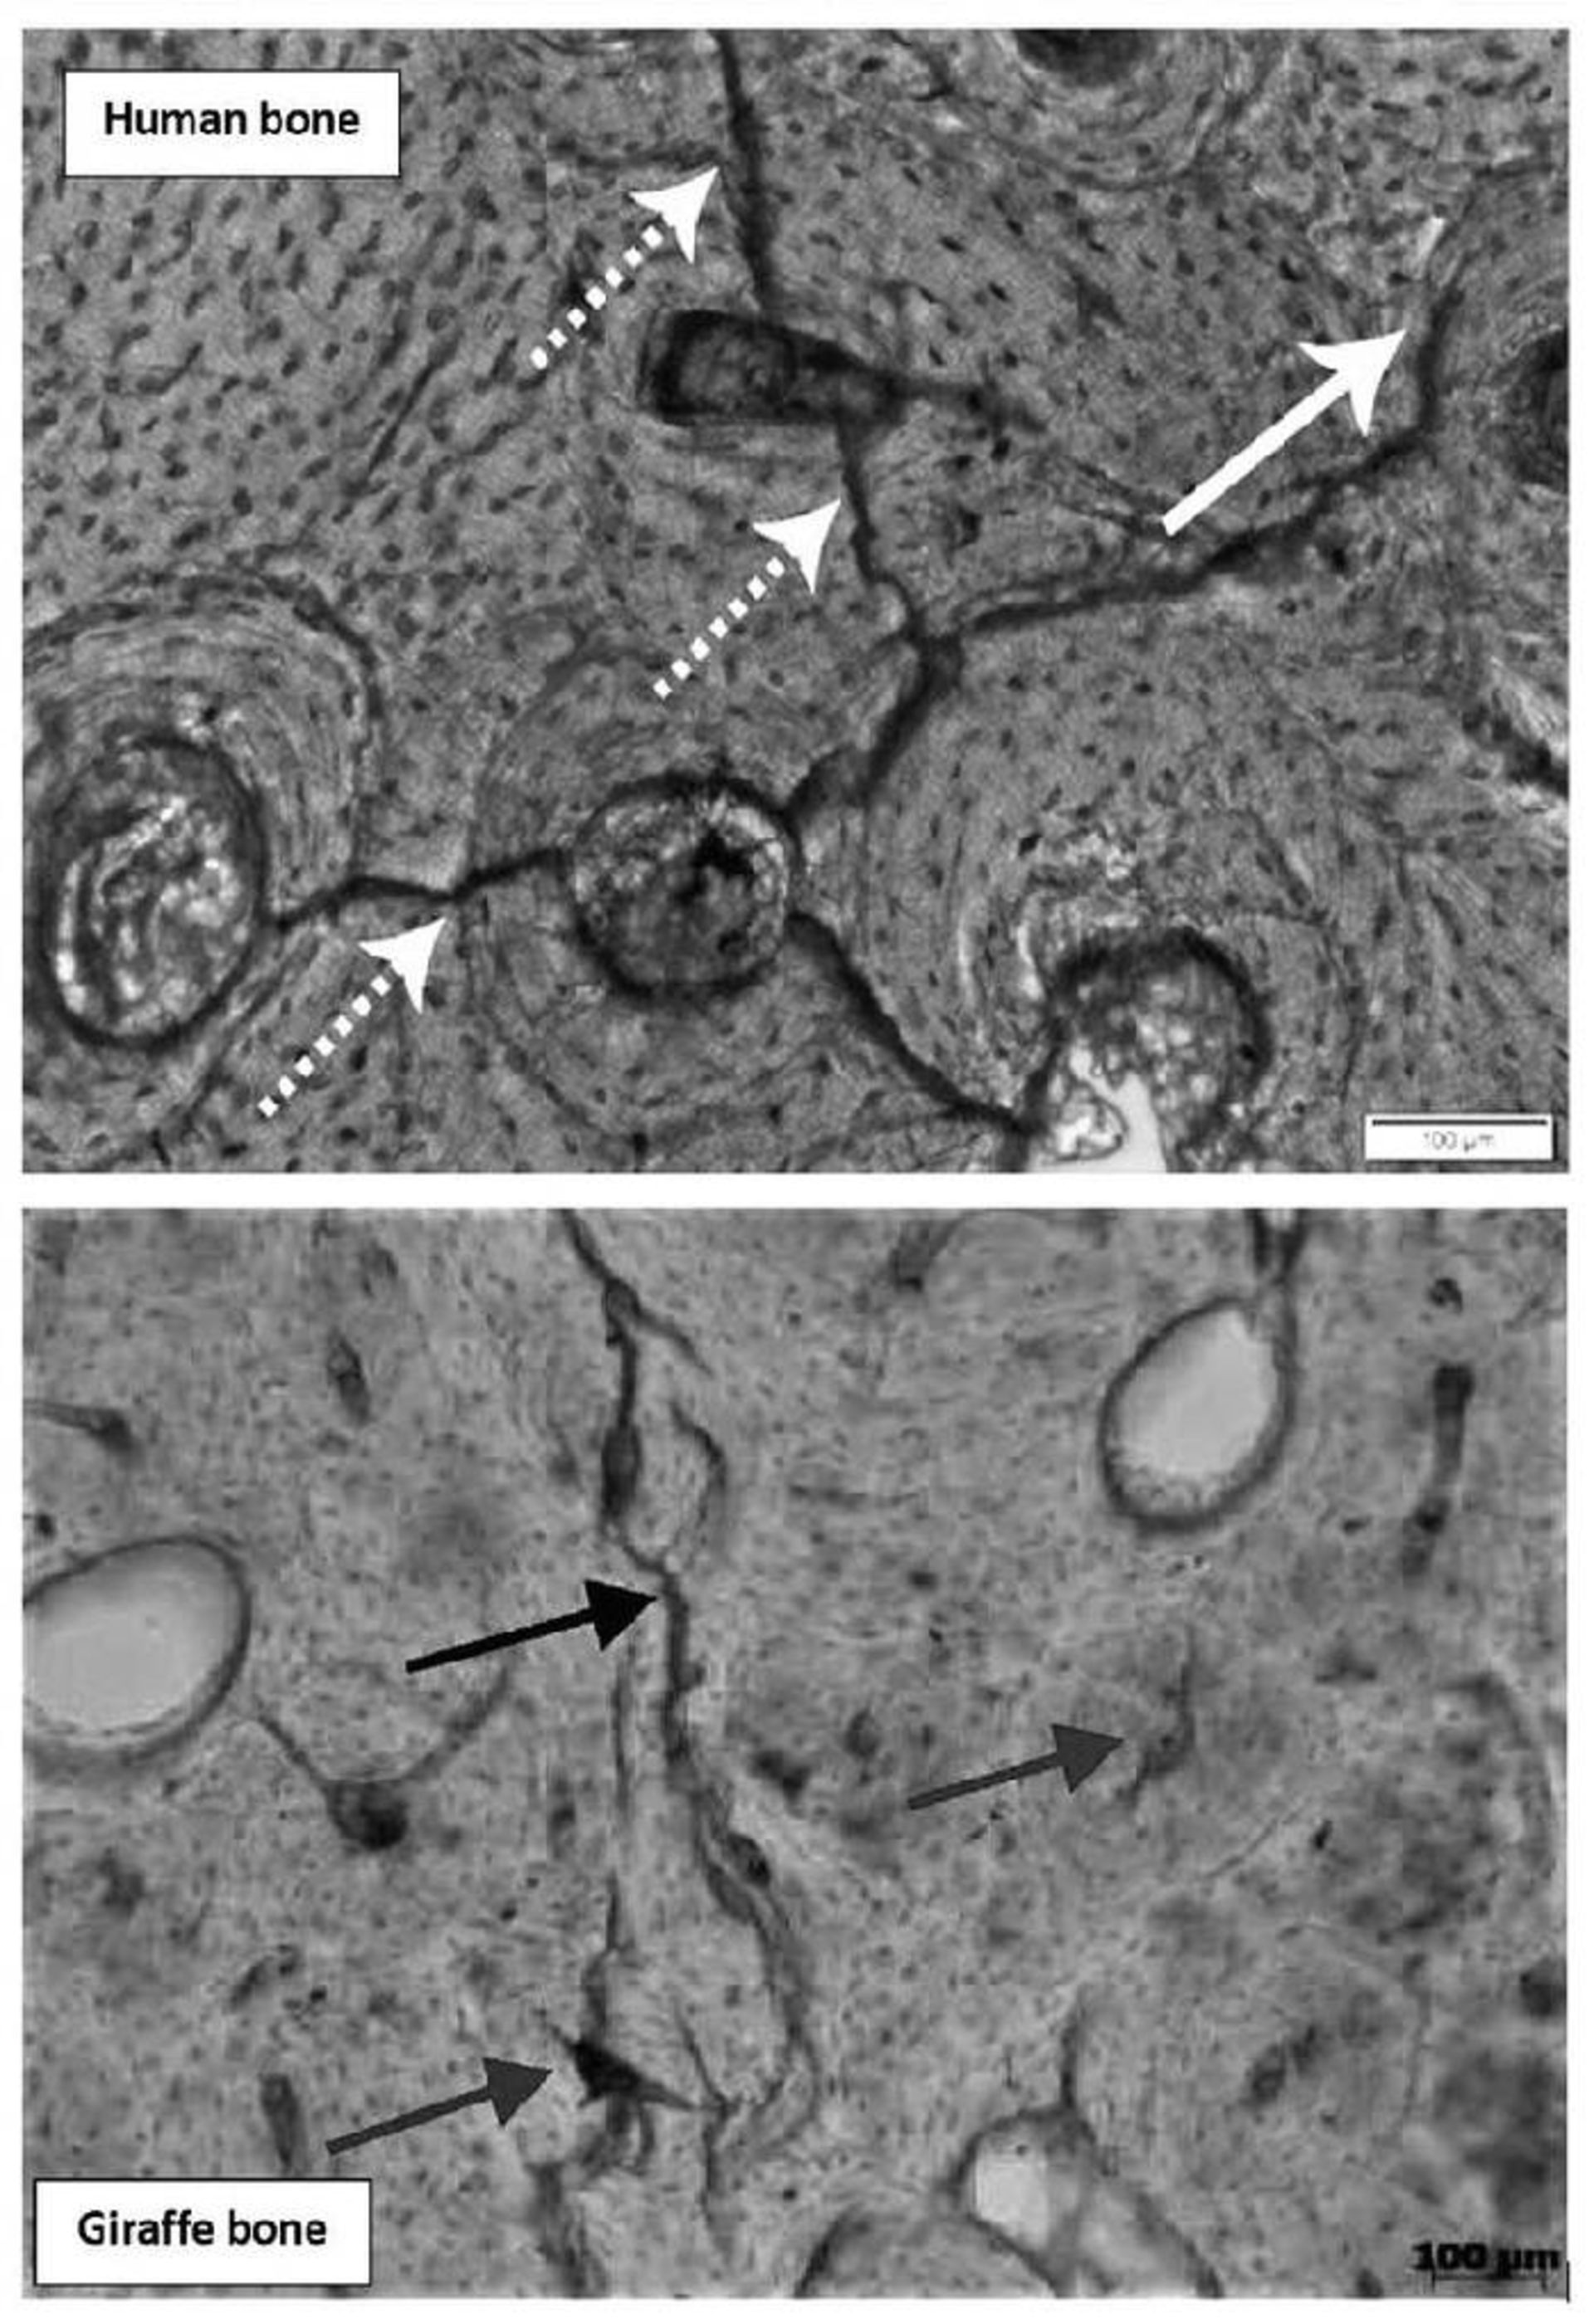

آسیب ناشی از رعدوبرق به شکل ترک‌هایی ظاهر می‌شود که از مرکز سلول‌های استخوان به سمت بیرون منشعب می‌شوند یا ترک‌هایی که به‌طور نامنظم بین خوشه‌های سلولی نمایان می‌شوند. الگوی آسیب یکسان است (بین انسان و حیوان)، حتی اگر ریزساختار استخوان انسان با ریزساختار استخوان حیوان فرق داشته باشد.

الگوهای ریزشکستگی‌ها و ریزضربه‌ها در استخوان انسان و استخوان زرافه

درحالی‌که الگوها یکسان هستند، شدت آن‌ها به منبع بستگی دارد و پژوهشگران در مقاله خود توضیح می‌دهند زرافه وحشی که به‌وسیله‌ی صاعقه واقعی کشته شده بود، ریزشکستگی‌های بیشتر و نامنظم‌تری نسبت‌به استخوان‌های انسان نشان می‌داد.